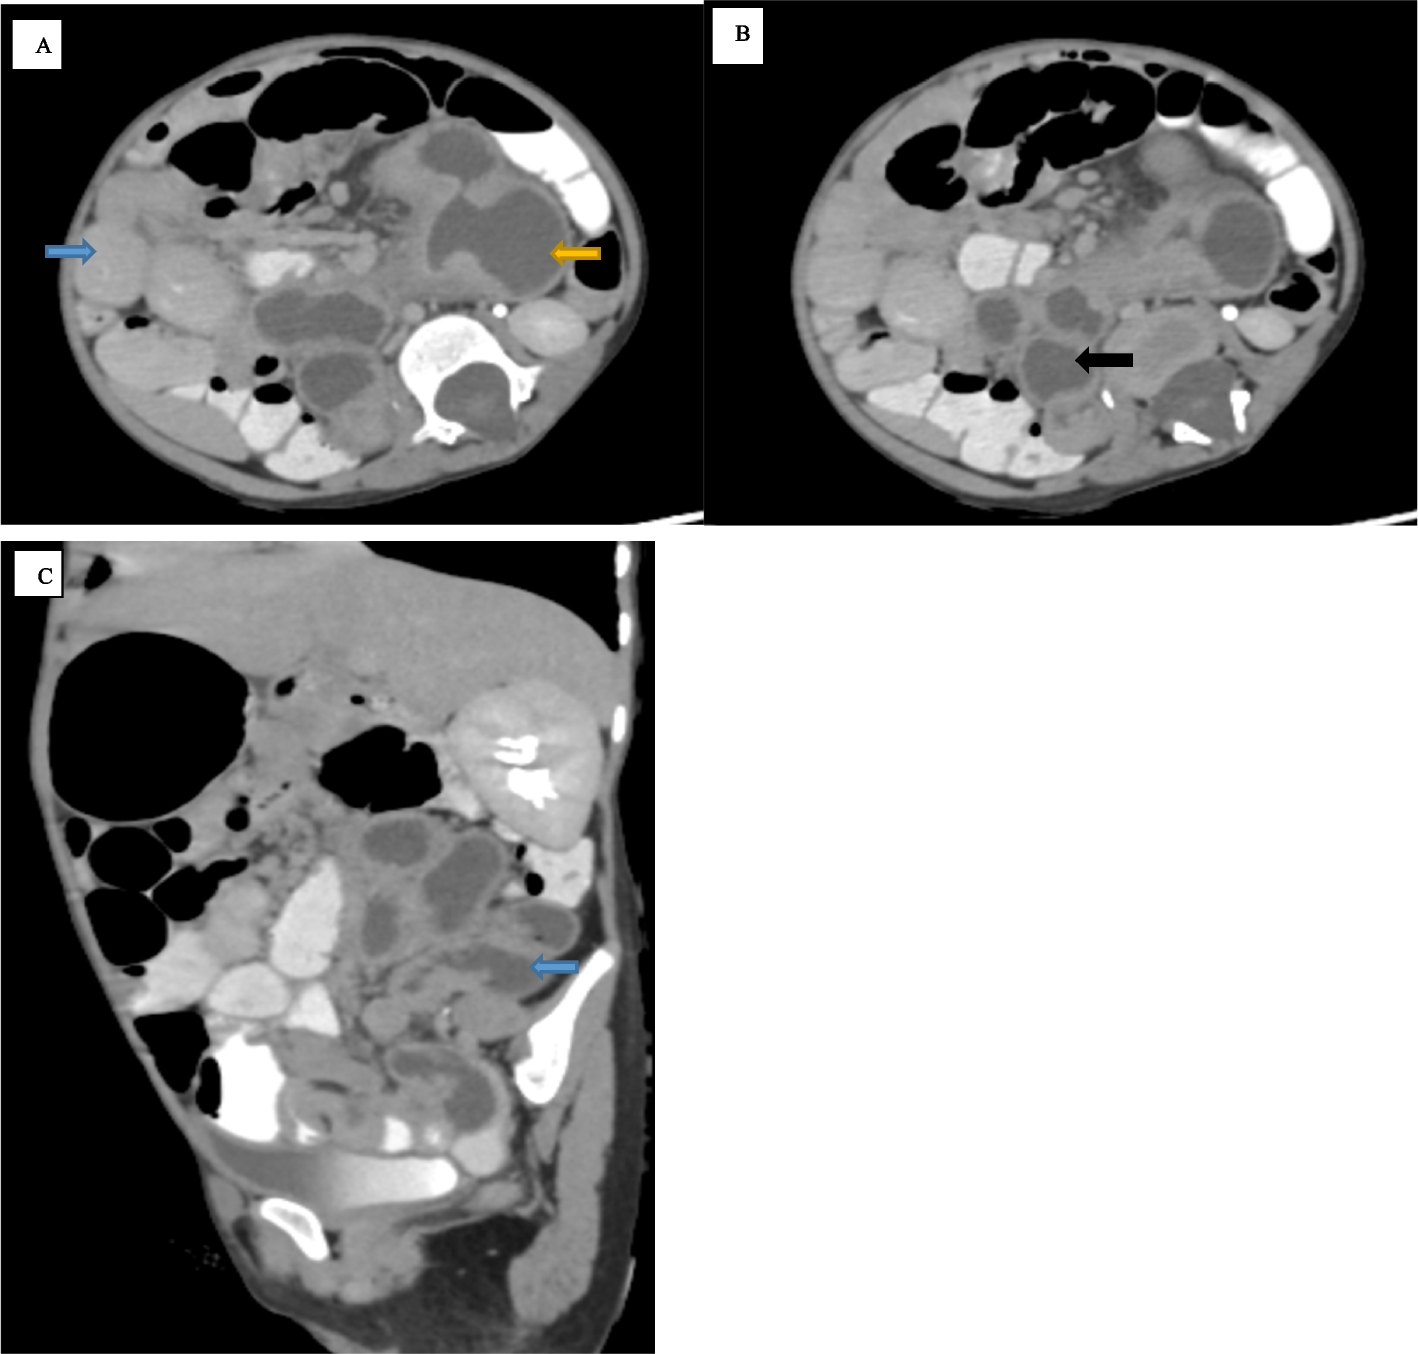

Case report: a rare cause of chronic abdominal pain and failure to thrive in a child — extensive gastrointestinal tract duplication cyst

Gastrointestinal tract duplication cyst is a rare congenital anomaly and can occur anywhere along the alimentary tract. Cl...

Management of uretero-colonic fistulas and ureteral injuries: a comprehensive surgical and endoscopic approach

Pediatric ureteral injuries can arise from trauma or surgical procedures, and urinary-enteral fistulas, although rare, are...